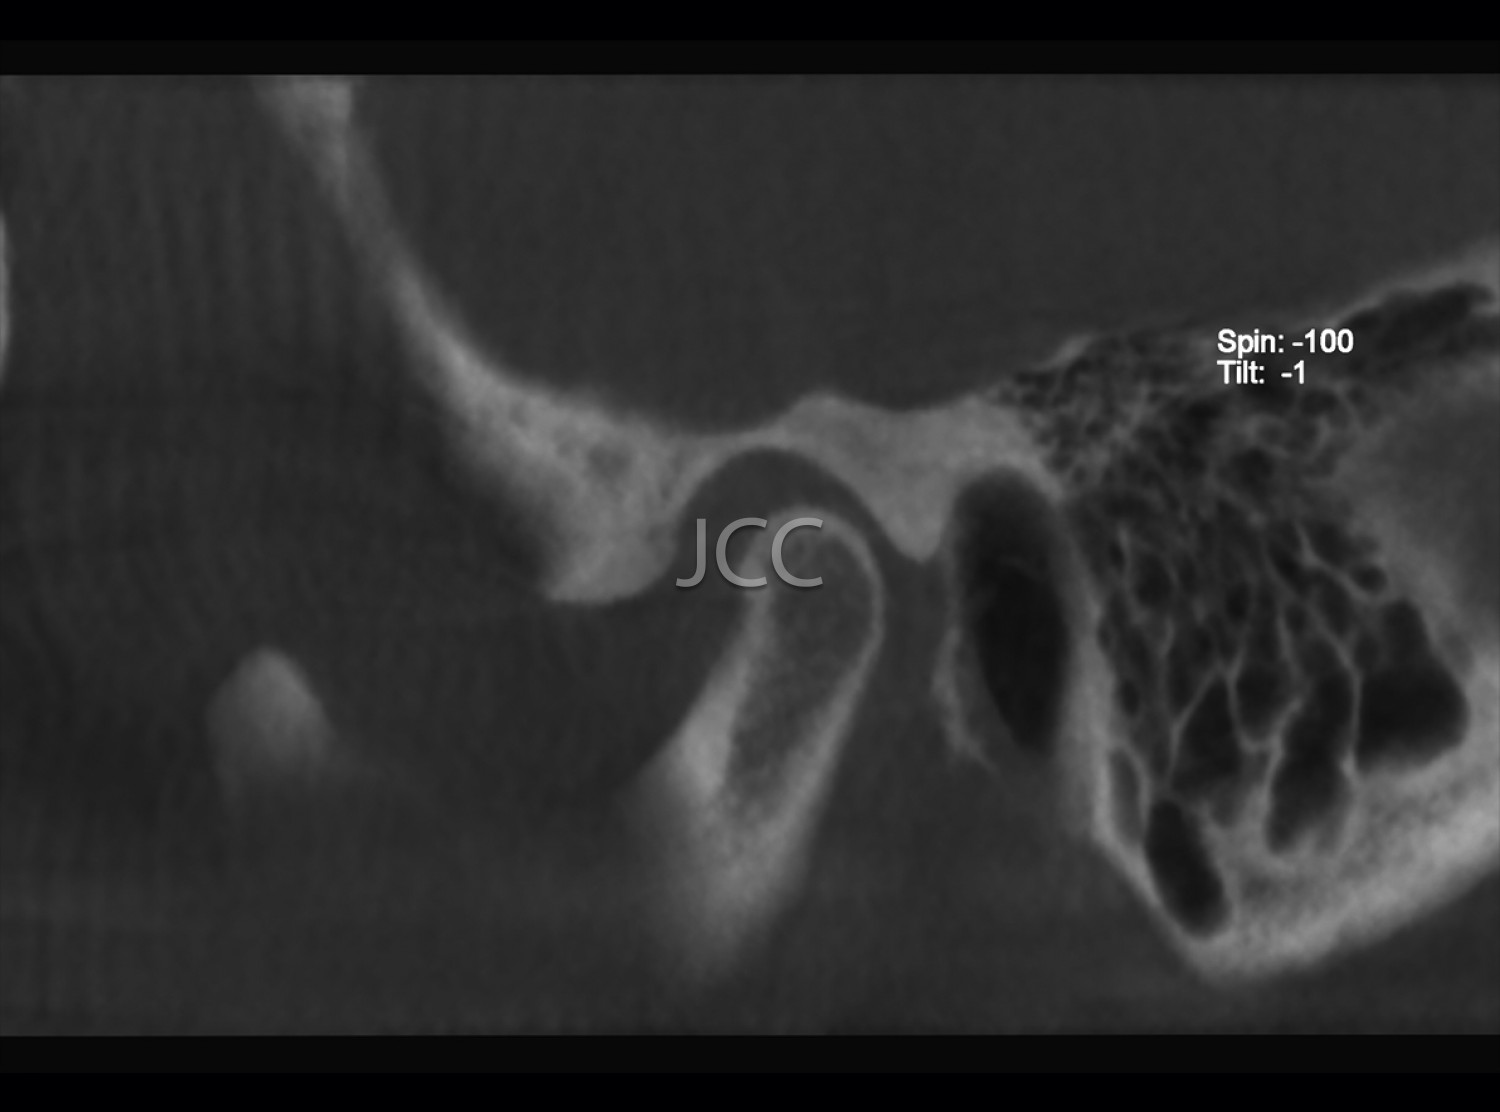

Dental Radiology - TMJ CBCT / CT

• Bone changes of the TMJ's

*Although preferably the CBCT mode is chosen, when one intends to analyse soft tissue pathologies, multi-cut CT is used.